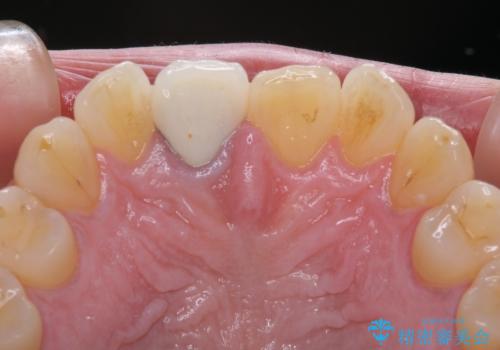

奥歯は虫歯が放置されていましたが、特に症状はなく歯髄の状態も正常でした。

前歯、奥歯ともにオールセラミッククラウンやセラミックインレーにて治療を行うこととしました。